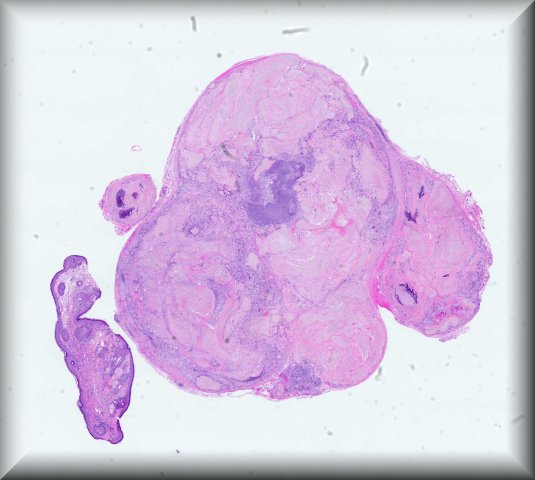

Jolique van Ipenburg (Nijmegen): 50-year-old male, retinoblastoma survivor, with conjunctival squamous lesion. Protocol |